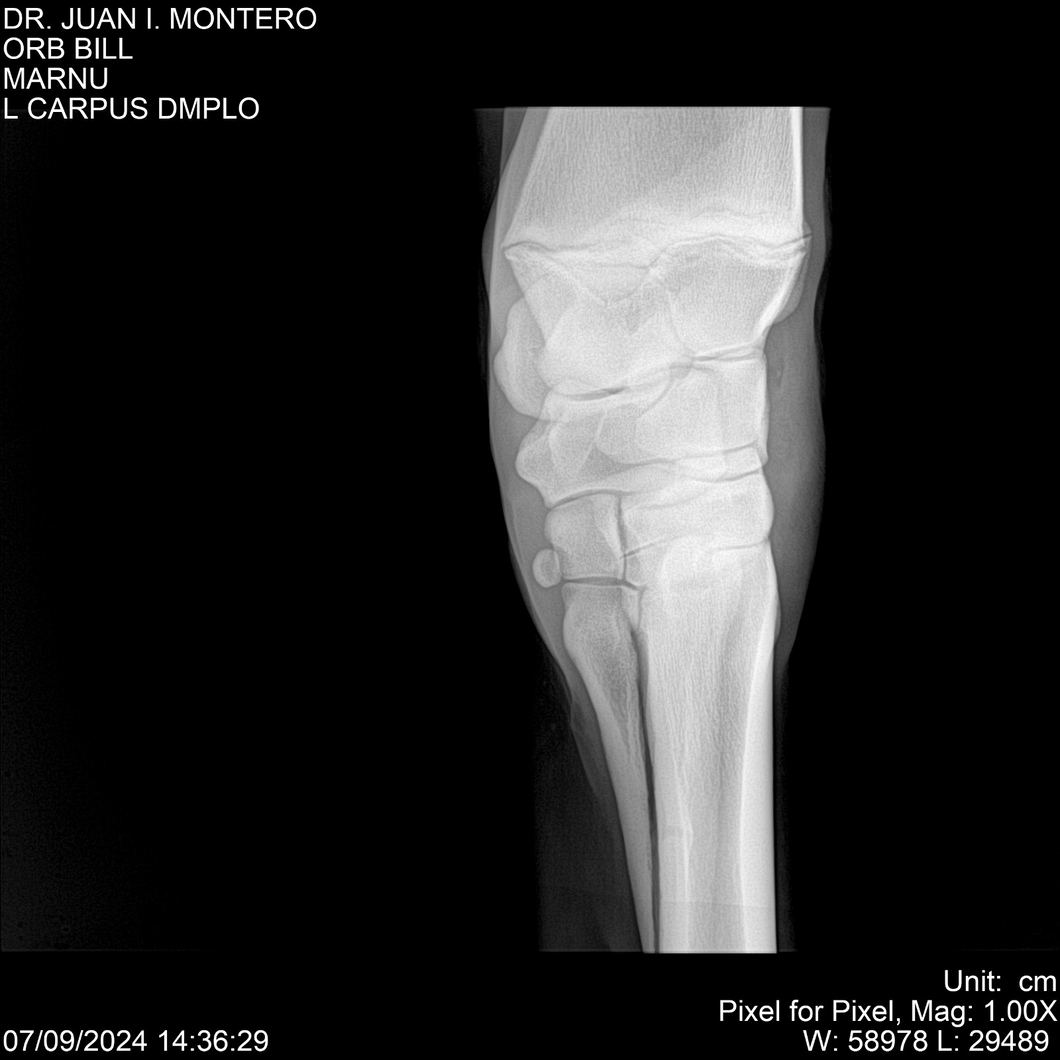

LOTE 7, ORB BILL 🔥 🔥 🔥 Lote Anterior Volver al remate Lote Siguiente Ficha Contacto Montevideo - Ficha del Lote Identificador: #282523 Categoría: Yeguarizos Montevideo - 83 Visualizaciones ClicData Contacto Empresa: Abelenda N. R., Walter Hugo Nombre*: Teléfono* : E-mail* : Mensaje Enviar Registrese gratis Este contenido Exclusivo está disponible sólo para usuarios registrados Ingresar